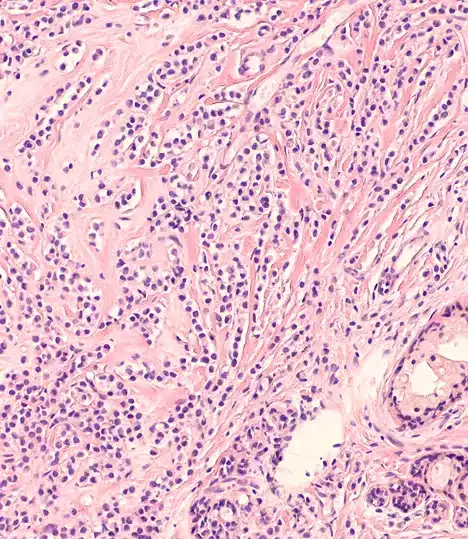

Soy el Dr. Gonzalo Ziegler y me dedico a brindar tratamientos quirúrgicos oncológicos personalizados en piel y mama.

Especialidades quirúrgicas en piel y mama

Cuento con una formación especializada en cirugía oncológica de piel y mama. Cada procedimiento que realizo está enfocado en brindar diagnósticos precisos y tratamientos seguros, adaptados a la necesidad de cada paciente para lograr resultados reales y duraderos.

Soy cirujano oncólogo en Lima con más de una década de experiencia en el diagnóstico y tratamiento de cáncer de mama, melanoma y otras enfermedades oncológicas de la piel. Me especializo en intervenciones quirúrgicas precisas y en el acompañamiento integral de cada paciente, brindando atención en la Clínica Ziegler, una institución comprometida con la salud y el bienestar.

Mi enfoque combina el uso de tecnología médica de última generación, atención cercana y un compromiso constante con la actualización científica. Si estás buscando un mastólogo en Lima o un especialista en tumores de piel, puedo ayudarte a tomar decisiones informadas y seguras para tu tratamiento.